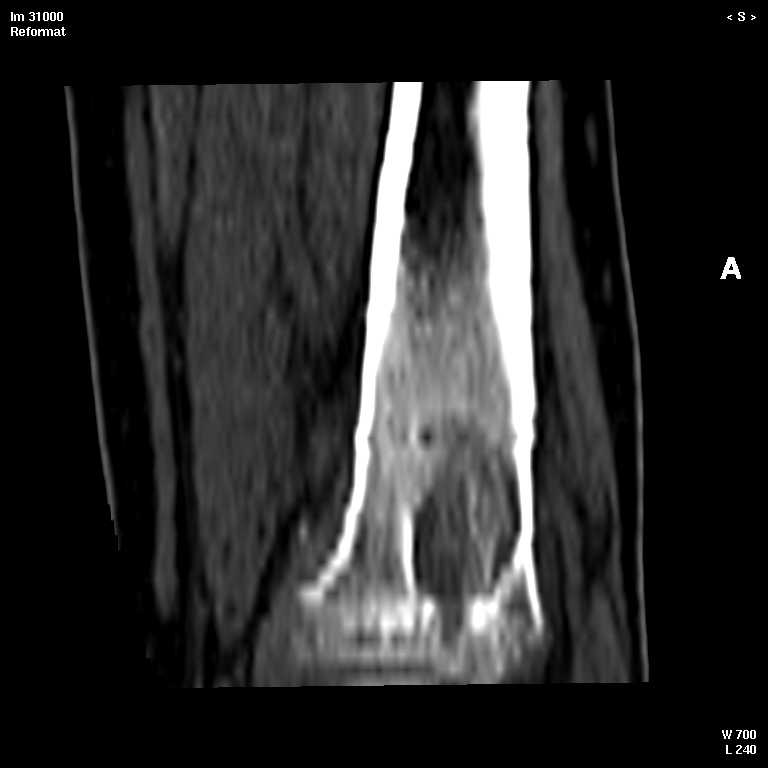

С подозрением на хондрому большеберцовой кости левой голени выполнена компьютерная томография. На серии томограмм получены изображения дистальных отделов левой голени. В дистальном метафизе на уровне нижней трети по латеральному краю определяется кортикальный очаг деструкции размерами 1,3x0,5x0,8 см. На уровне очага деструкции отмечается истончение кортикального слоя, без признаков его разрушения. Кость на уровне очага вздута. Структура окружающих мягких тканей не нарушена, объемных образований не определяется. Крупные нервные стволы и просветы крупных сосудов хорошо дифференцируются. Кожа и подкожно-жировая клетчатка не изменены.Заключение: КТ - признаки кортикального остеолитического очага деструкции в дистальном отделе метафиза левой большеберцовой кости без признаков разрушения кортикального слоя (остеогенная саркома?).19.11.2002 г. осмотрена онкологом, выставлен диагноз: саркома левой большеберцовой кости?Лабораторные исследования: - ОAK от 06.11.2002 г. - L - 11,3х109; эр. - 4,47хЮ12; НЬ - 117 гр./л; Ht - 33,6%; тр. -208x109; СОЭ - 38 мм./час, э-1; п-7; с-55; м-4; л-33.В отделении детской онкологии 11.12.02 выполнена операция: секвестр-некрэктомия н/3 левой большеберцовой кости.Послеоперационный период без осложнений.Проведено лечение. Линкомицин 150 мгхЗ р./д., обезболивание (анальгин, димедрол). Швы сняты 23.12.02, заживление первичным натяжением.Получен результат гистологического исследования: хронический остеомиелит. Данных за онкопроцесс нет.На приеме врача ортопеда поликлиники с жалобами на усиление болевого синдрома 03.01.03. Наложена задняя гипсовая лангета. Назначен противовоспалительная терапия, препараты Са и кальцийтониновые препараты. На фоне проводимого лечения болевой синдром купировался. На серии рентгенограмм (январь-февраль-март) На нижней трети левой большеберцовой кости наличие дополнительного кортикального очага диструкции с размерами 1.5x0,5 см., в динамике отмечается увеличение в размерах.С подозрением на рецидив хронического остеомиелита большеберцовой кости левой голени выполнена компьютерная томография.19/03/2003 На серии томограмм получены изображения дистальных отделов нижней трети левой голени и мягких тканей.В метафизе определяется очаг деструкции с четкими, неровными контурами, неоднородной структуры, за счет костных балок, размерами 1.8x1.8x2,4 см, плотностью 29 ед Н.В дистальном методиафизе. по латеральному краю, определяется кортикальный очаг деструкции, размерами 0,6x0,5x2,0 см, неоднородной структуры, за счет наличия фиброзных и костных балок, кортикальный слой истончен, без признаков разрушения.Структура окружающих мягких тканей не нарушена, объемных образований не определяется. Крупные нервные стволы и просветы крупных сосудов хорошо дифференцируются.Кожа и подкожно-жировая клетчатка не изменены.ЗАКЛЮЧЕНИЕ:КТ-картина состояния после операции. Формирование постоперационной, внутрикостной кисты. КТ-признаки объемного образования нижней трети левой большеберцовой кости, вероятнее всего фиброзная дисплазияРЕКОМЕНДАЦИИ: МРТ левого голеностопного сустава с захватом нижней трети голени.Лабораторные исследования: OAK от 05.03.2003 г. - L v 7.0х109; эр. - 4,74хЮ12; НЬ - 130 гр./л; Ht - 37%; тр. -274x109; СОЭ - 4 мм./час, э-1; п-1; с-53; м-3; л-42.Вопросы: уточнение диагноза? (хр.остеомиелит, обострение? Или все таки онкопроцесс) какие исследования провести? тактика лечения? КТ-снимки во вложении. Заранее благодарен!С уважением, Н.П.Козел.